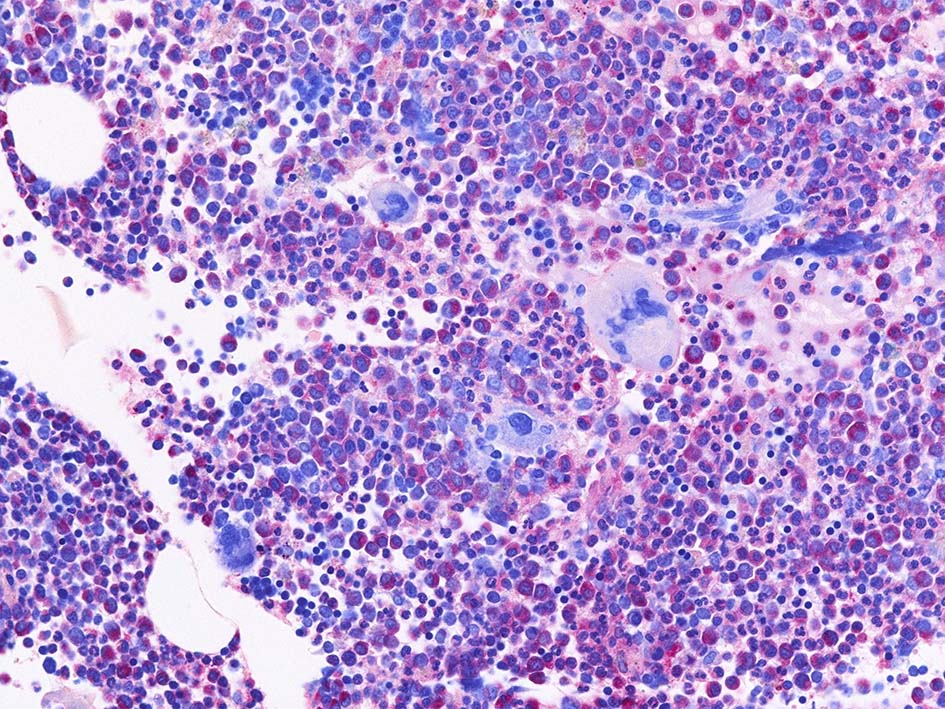

Naphtohl-ASD-CAE Fig.01

Fig.01: hypercellular marrow. ASDで赤染する細胞の増加=granulopoietic hyperplasiaがある.

Fig.02: 幼若な顆粒球が増加している. 赤芽球は散在しており血島は不明瞭である. 過形成髄なのにFig.02に成熟大型巨核球はみられない.

Fig.03: granulopoietic hyperplasia. 成熟顆粒球の増加もある.